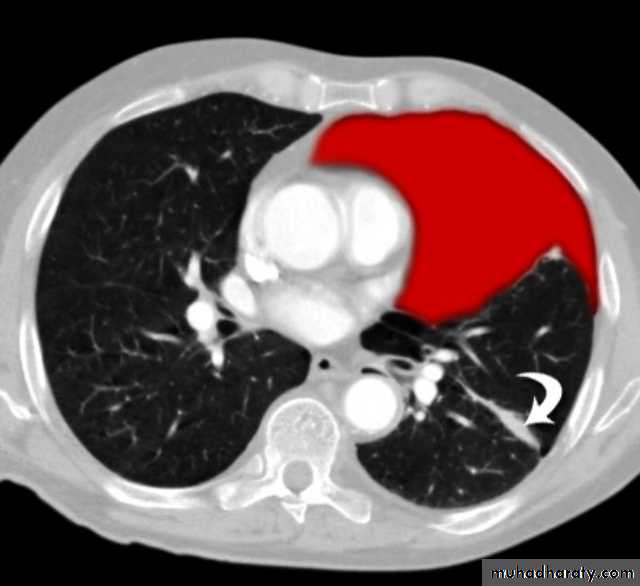

Secondary metastasis

Old age group above 50 Y , any lesion within the cerebellar hemisphere it is secondary metastasis unless proven otherwise F. from breast CA M. from bronchogenic CA .

Appear as nodular single or multiple lesion hypo dense or hyper dense .

Surrounded by per focal edema

Enhanced as solid or ring pattern of enhancement .